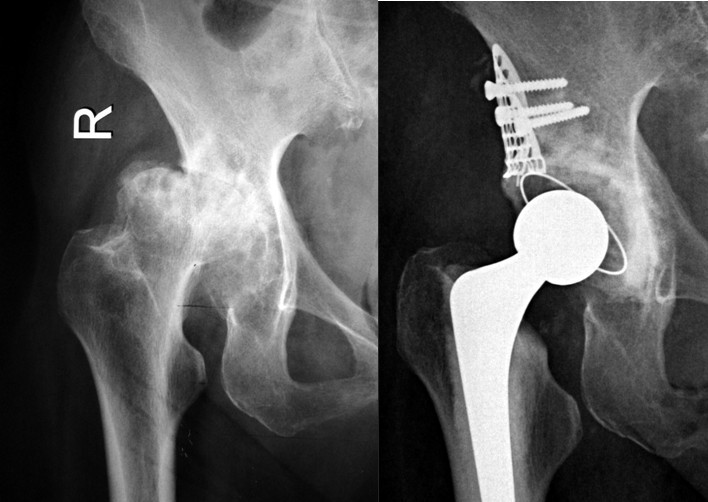

⑴Ⅰ型缺损:髋臼发育不良合并骨性关节炎,髋臼上缘Ⅰ型骨缺损,以金属网包含上缘缺损螺钉固定后,打压植骨,三代骨水泥技术全髋关节置换。